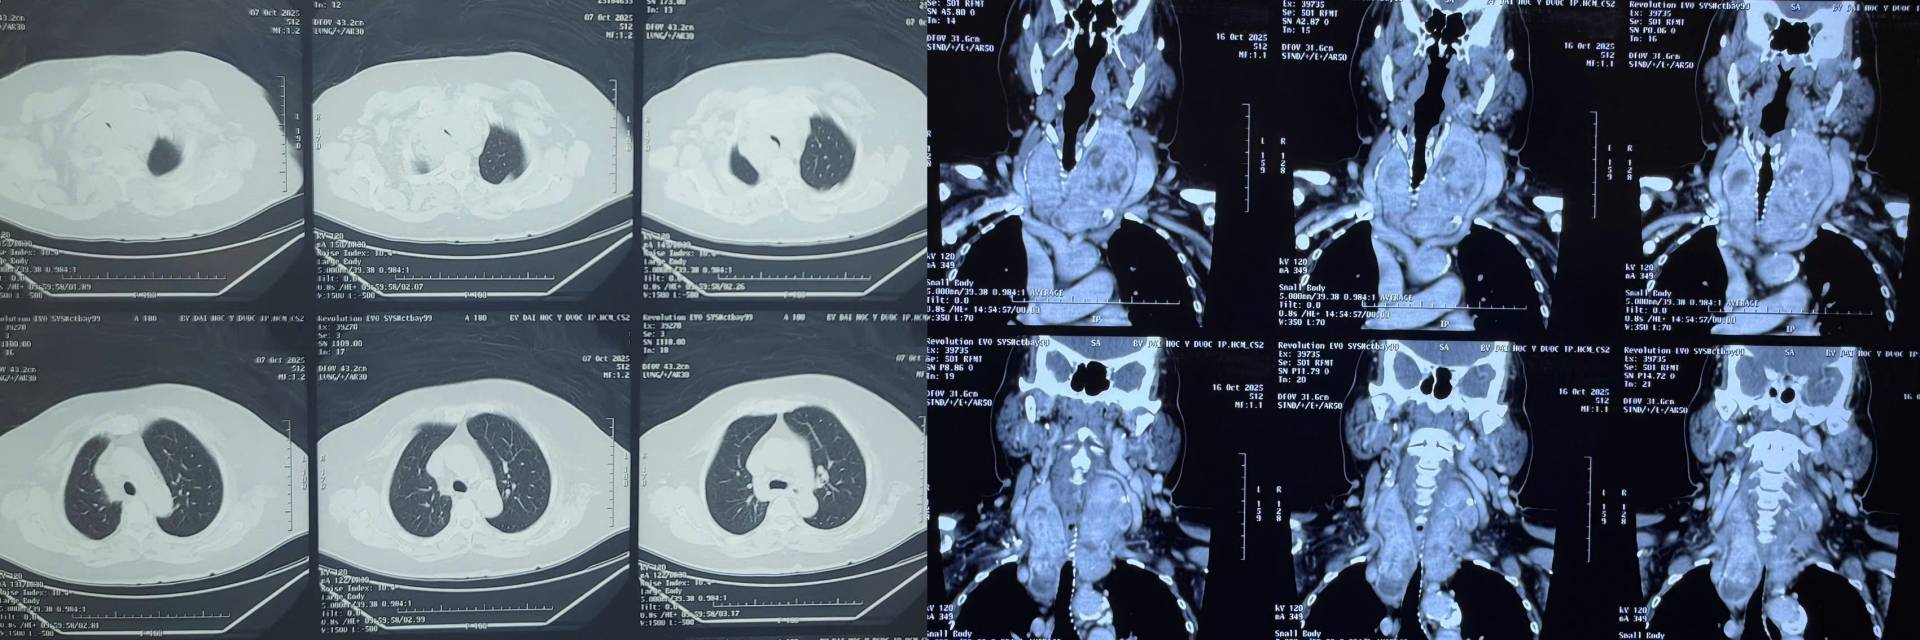

Kết quả kiểm tra cho thấy bà bị bướu giáp thòng trung thất kích thước lớn, chèn ép gần như toàn bộ khí quản, khiến việc hô hấp vô cùng khó khăn.

“Đây là một ca mổ không hề đơn giản. Bướu giáp thòng xuống sâu, ôm sát khí quản và các mạch máu lớn trong trung thất. Chỉ cần sơ sẩy, bệnh nhân có thể mất đường thở ngay trên bàn mổ. Nhưng may mắn là ca phẫu thuật diễn ra thuận lợi, chúng tôi đã lấy trọn khối bướu, giải phóng hoàn toàn đường thở cho bệnh nhân.”